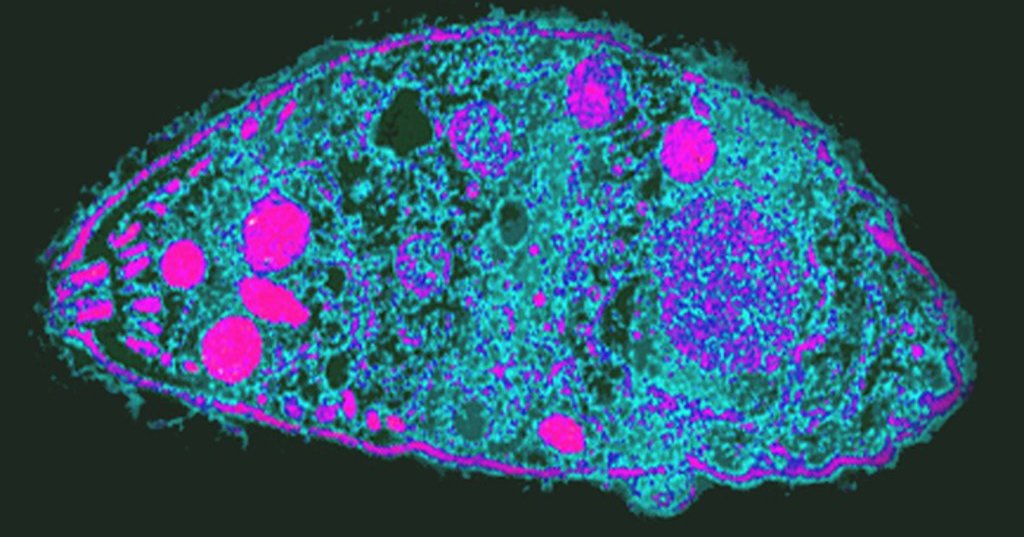

Кошачьи паразиты делают из людей лучших бизнесменов

В статье, опубликованной в Proceedings of the Royal Society B, ученые описывают, как они выявляли возможные изменения в поведении, способные произойти из-за Toxoplasma gondii, и что в результате нашли.